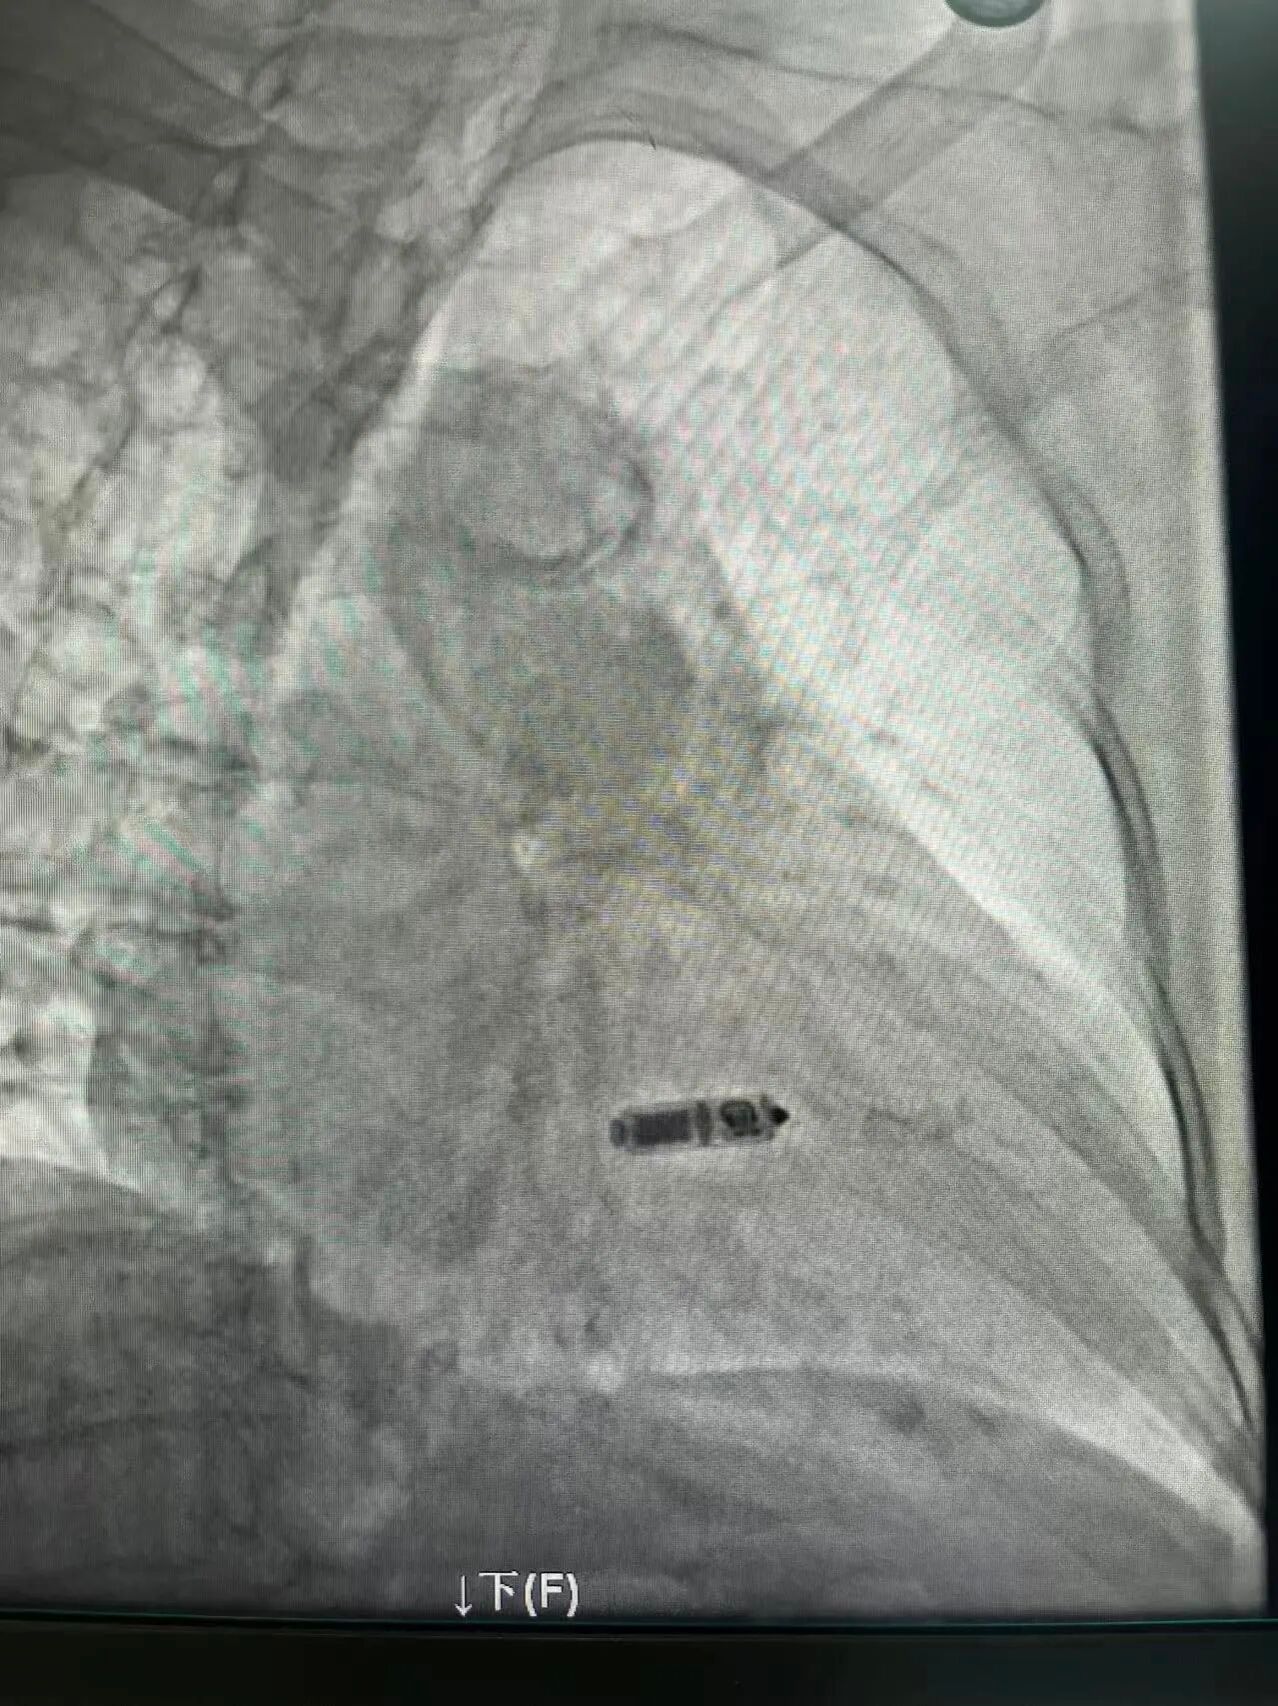

近日,我院心血管内科起搏电生理团队在王俊莉主任的带领下,成功为一名75岁三度房室传导阻滞的老年女性患者实施了无导线双腔起搏器植入术。该手术的成功开展,标志着我院在心律失常器械治疗领域取得了突破,正式迈入了“无线起搏”的新时代,为区域内心动过缓患者提供了更优、更前沿的治疗选择。

手术当日,王俊莉主任带领电生理团队成员在介入导管室紧密配合下,手术紧张而有序地展开。凭借丰富的手术经验和娴熟的导管操控技术,术者通过递送系统将微小的起搏器精准地送至患者右心室的中位间隔部。术中反复测试各项参数均表现优异,心房感知良好,实现了稳定的房室同步收缩。整个手术时长短,出血量极少。患者术后感觉良好,困扰多日的头晕症状消失,对治疗效果非常满意。

起搏器仅如一粒维生素胶囊大小,重量约2克,通过股静脉穿刺,直接植入在患者右心室及心房感知位点,避免了传统起搏器在胸前皮下制作囊袋及植入电极导线所带来的创伤、感染、导线脱位、断裂、静脉血栓形成等与导线相关的并发症风险。